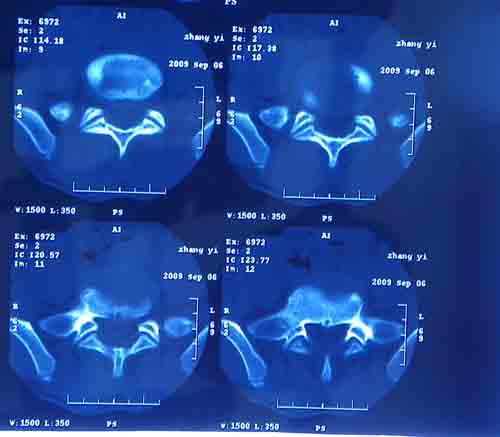

腰5/骶1椎间膨突出外,还有点异常,不知是什么东东,请各位大虾帮忙看看(12骨窗最明显)

椎体后缘软骨结节

软骨结节

支持 椎体后缘软骨结节。